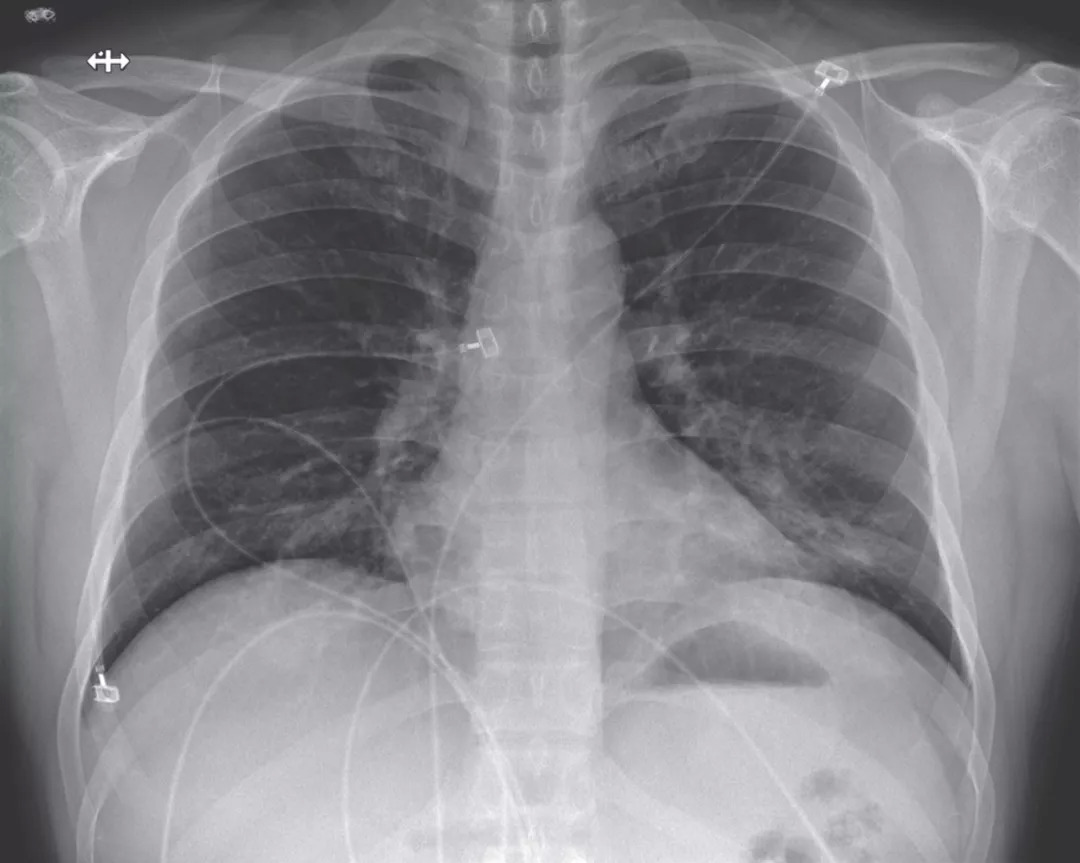

在医院第6天,第四次胸部X射线照片显示两个肺中都有基底条状混浊,这一发现与非典型肺炎相符(图5),并且在听诊时在两个肺中都出现了罗音。鉴于放射线影像学发现,决定给予氧气补充,患者持续发烧,多个部位持续出现2019-nCoVRNA持续阳性的情况,并发生了严重肺炎。

图五